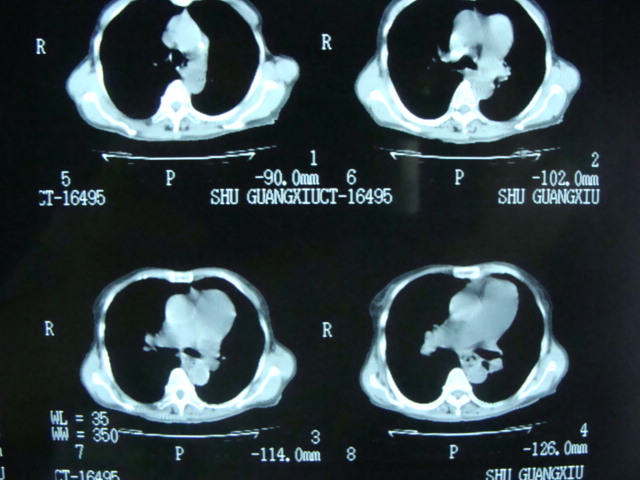

标题: CT13799:风心?肺动脉发育异常?

xxx女.72岁,胸闷不适,一侧下肢水肿.肺窗没见异常.不上传.

肺动脉根部,右室增宽;肺门小;是什麽征象///

右肺动肺截断.肺动肺脉高压

我看食管下段管腔狭窄,壁明显厚,腹水,肝右叶低密度灶

食管癌?肝转移?腹水

主肺动脉扩张,腹水.

考虑:1、肺动脉高压(原因?);

2、肝硬化伴腹水。